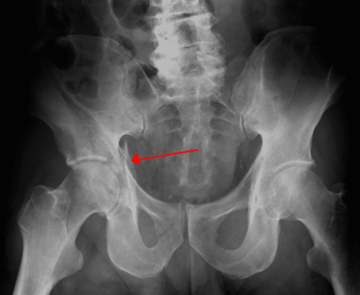

الأشعة السينية (AP، ومناظير Judet) قد تكون الخطوة الأولى.

إلا أن التصوير المقطعي CT هو المعيار الذهبي للتشخيص، إذ يحدد نمط الكسر وامتداده بدقة ويُستخدم لتخطيط العلاج الجراحي.